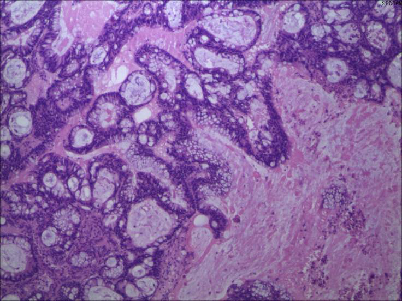

肠镜病理:直肠腺癌

直肠中分化腺癌,癌组织浸润肠壁全层至肠壁外脂肪组织,未穿透外膜层。LN1/3

(盆腔肿物)约15X10X3cm,切面灰白,质脆,镜下:可见卵巢结构,其内见腺癌浸润。免疫组化:癌细胞CK20(+),CK(+),CDX-2(+),M-CEA(+),Villin(+),TTF-1(-),CK7(-)。符合直肠腺癌卵巢转移。